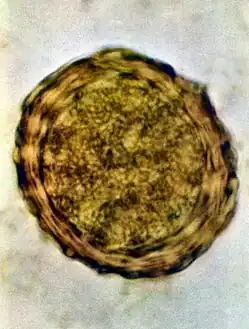

Infertile egg

Ascaris lumbricoides is characterized by its great size. Males are 2–4 mm (0.08–0.2 in) in diameter and 15–31 cm (5.9–12 in) long. The male's posterior end is curved ventrally and has a bluntly pointed tail. Females are 3–6 mm (0.1–0.2 in) wide and 20–49 cm (7.9–19 in) long. The vulva is located in the anterior end and accounts for about one-third of its body length. Uteri may contain up to 27 million eggs at a time, with 200,000 being laid per day. Fertilized eggs are oval to round in shape and are 45–75 μm (0.0018–0.0030 in) long and 35–50 μm (0.0014–0.0020 in) wide with a thick outer shell. Unfertilized eggs measure 88–94 μm (0.0035–0.0037 in) long and 44 μm (0.0017 in) wide.[9]